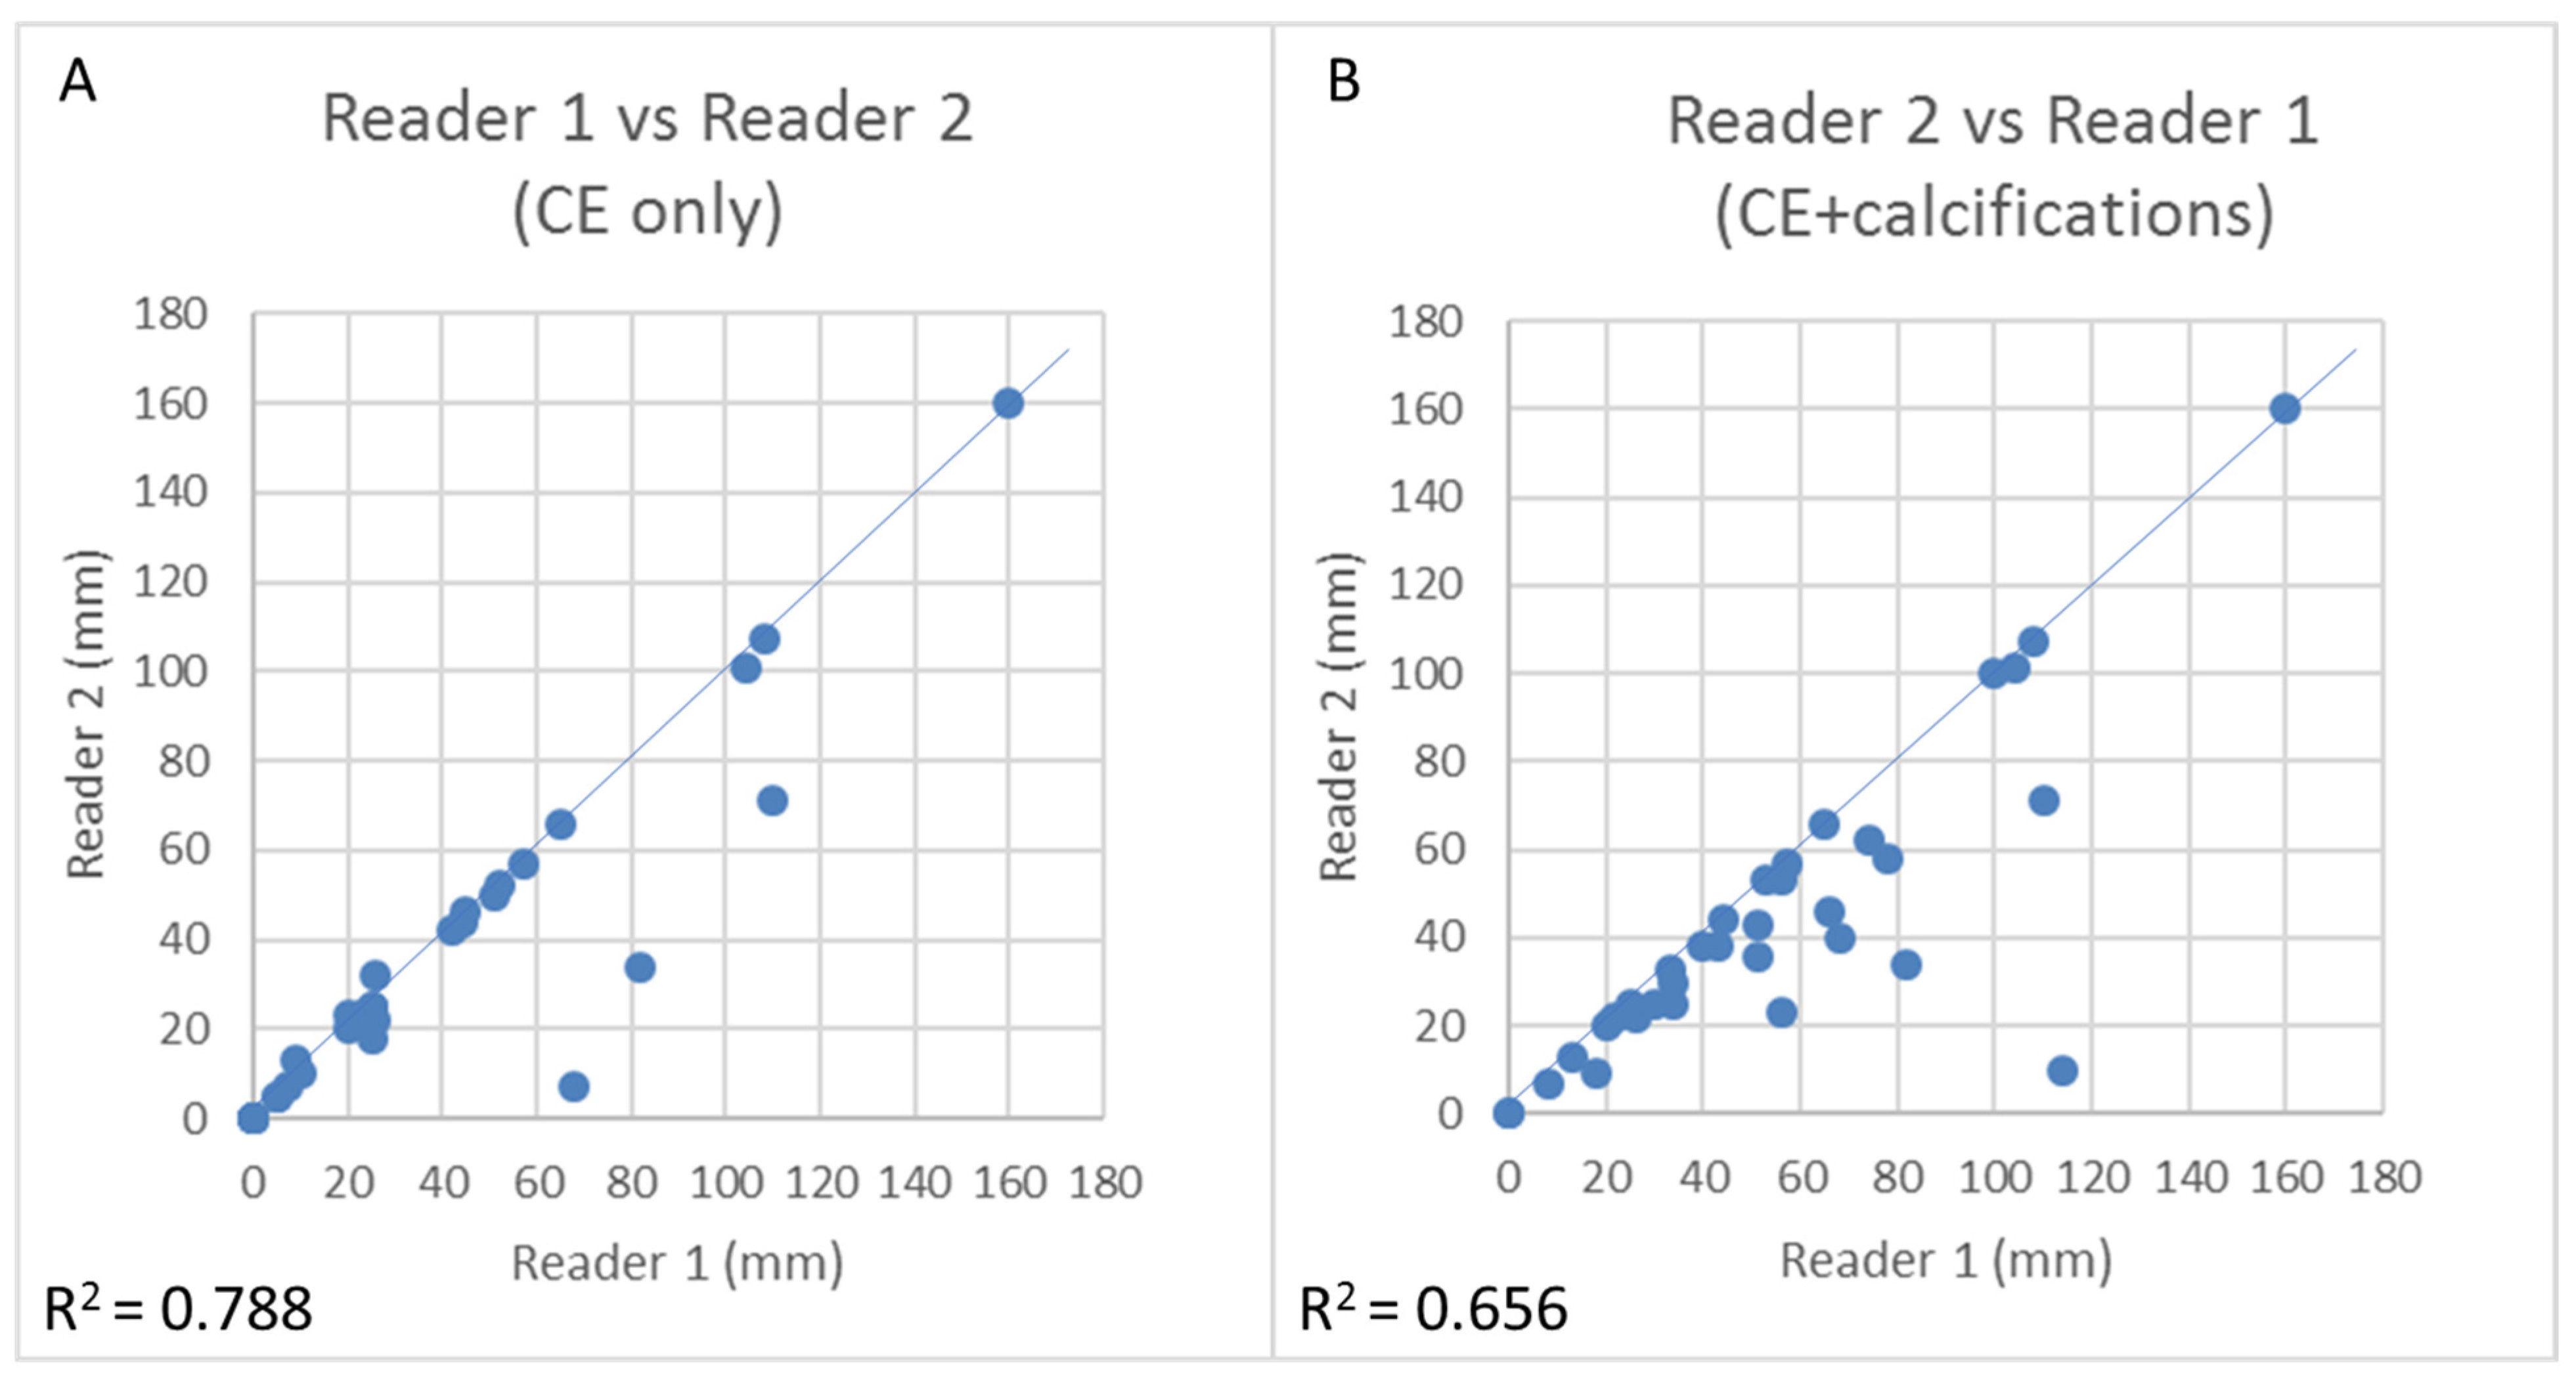

3.5. CEM Reproducibility